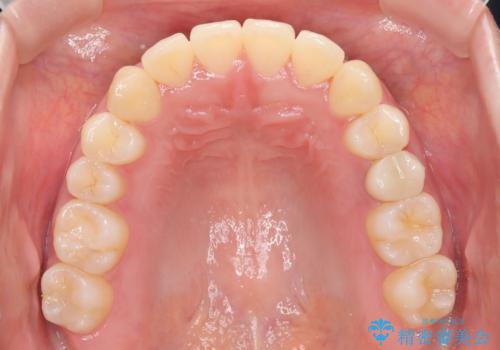

- 前歯のガタツキが気になるとのことで来院されました。

ワイヤー矯正とインビザライン矯正を併用することによって、治療期間の短縮と、より良い仕上がりを目指す治療を選択することとしました。

インビザライン(アライナー)矯正とワイヤー矯正のそれぞれの利点を生かした治療を行い、綺麗な歯並びになりました。